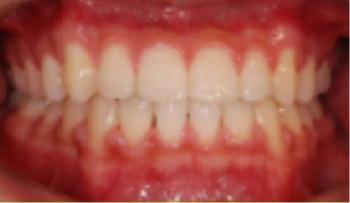

교정치료 Before&After

• 상하악전돌 위턱과 아래턱이 앞으로 나와 입이 돌출됨.

Before

After